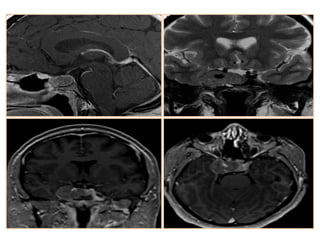

Chordoma and Chondrosarcoma Chondromatoustumors develop from embryonic cartilaginous remnants enclosed in the bones of the skull base. They often arise from the petrooccipital or sphenooccipital synchondrosis and destroy the adjacent bones. Chondromatous tumors can be hypoattenuating at CT, possibly with a marginal high- attenuation area due to a dense matrix of hyaline cartilage or massive calcification. Lytic bone erosion may be seen. At MR imaging, the tumor is hypointense on T1- weighted images and heterogeneously hyperintense on T2-weighted images; it enhances poorly due to its hypovascularity.

• #23 Tolosa Hunt syndrome: axial (a) and coronal (b) T2-wi, sagittal (c) enhanced CT, showing a insular hypointense enlargement of the left cavernous sinus (arrows) with an enhancement and an extension to the orbital apex (star on image c). These findings are consistent with a Tolosa Hunt syndrome.

• #24 Tolosa-Hunt SyndromeT2 iso-hypointense signal in the left cavernous sinus with enhancement Enhancement is also seen in the left superior orbital fissure